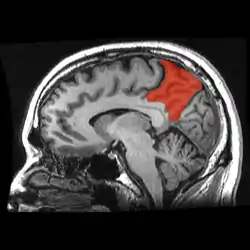

![]() Sagittal MRI slice with the precuneus shown in red. (Anterior to the left.) | |